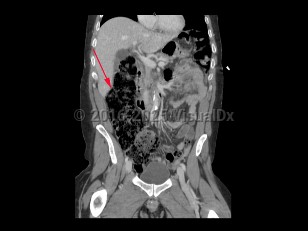

A large bowel obstruction (LBO) occurs when intraluminal contents fail to pass through the large intestine. This results in dilation of the proximal large bowel, with fluid accumulation, gas production, increased intraluminal pressure, and bacterial overgrowth. Bacterial translocation can then lead to bacteremia and sepsis.

LBOs may be partial or complete. A simple LBO is characterized by a single point of obstruction. A closed-loop obstruction is characterized by occlusion of the bowel at 2 points and has the highest risk of ischemia due to occlusion of the blood supply. A classic example of this is sigmoid volvulus. A competent ileocecal valve may also contribute to closed loop obstructions as the large bowel cannot decompress proximally.

Patients present with severe abdominal distension and inability to pass stool or flatus. Abdominal pain due to LBO is typically less severe and more gradual in onset compared to SBO. However, patients with LBO typically have more severe distension compared to SBO, as well as nausea and vomiting.